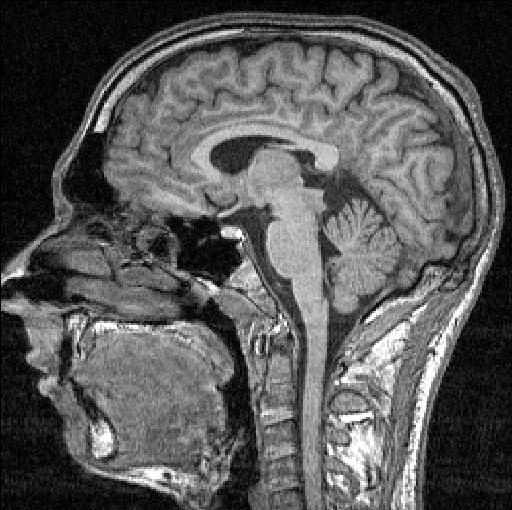

Joe's brain.

Chapter 7: Joe goes to visit Dr. Wanda Klein, the psychiatrist. Talking to the doctor is helpful to Joe. He finally is able to think clearly about the events of the past week and he reaches a decision about what must be causing all the strange events at work. But just when all becomes clear, Joe collapses into incoherency and Dr. Klein sends him to a hospital to recover.

Chapter 8: Joe spends two weeks in the hospital while the doctors try to understand what is wrong with his brain. Chloe visits Joe, but their conversation causes Joe to have another seizure.